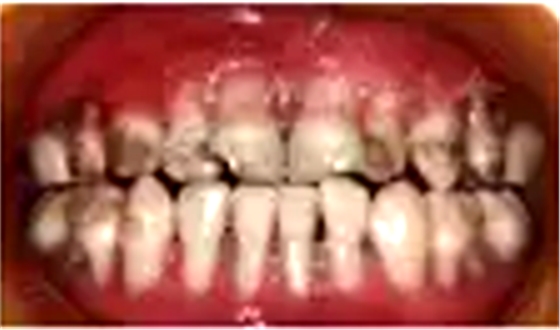

口腔??茩z查:口腔黏膜光滑,全口唇頰側(cè)牙齦重度萎縮,牙根暴露,探診易出血,牙齒表面可見齲壞及色素沉著,口腔衛(wèi)生可。遠(yuǎn)中切角缺損,Ⅱ度松動,唇側(cè)牙齦萎縮至根中1/3伴腫脹;Ⅱ度松動,唇側(cè)牙齦萎縮至根中1/3伴腫脹;冠完整,Ⅲ度松動,唇側(cè)牙齦萎縮至根尖1/3,齦乳頭及舌側(cè)牙齦萎縮程度較唇側(cè)輕(圖1)。

圖1 重型先天性中性粒細(xì)胞缺乏癥患者口內(nèi)照片